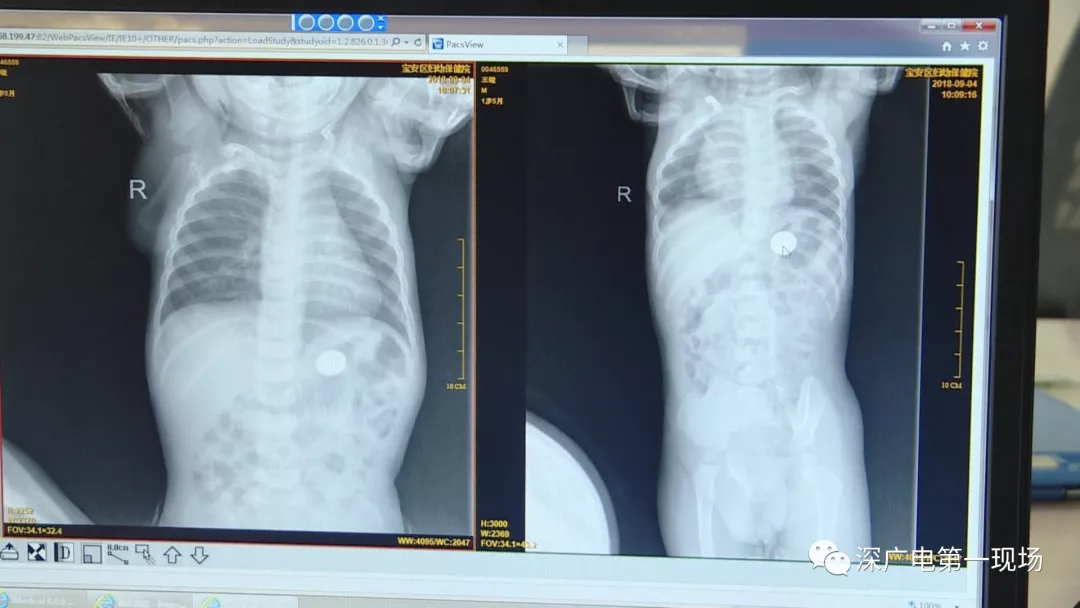

因祸得福!1岁男童摔伤送院 医生竟从胸片中发现了这个…